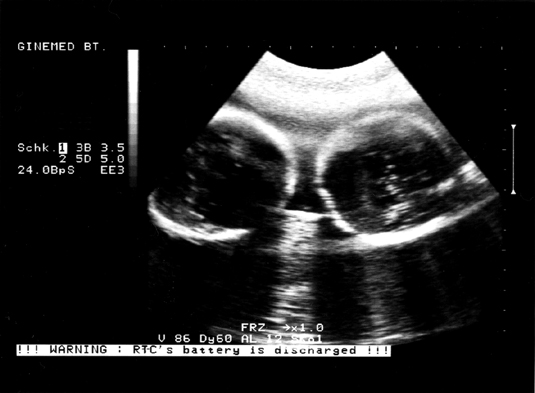

Mi tegnap voltunk a magánrendelőben vizsgálaton és UH-n.

(Odafelé elképesztő fülledt kánikula, visszafelé meg úgy zuhogott az eső - hőmérséklet változatlan - mintha dézsából öntenék - de igazán kellemes érzés volt amig eljutottunk az autóig.)

A bébikkel minden a lehető legnagyobb rendben, méhszáj is teljesen zárt, minden OK. :D :D

Mindegyik UH-n más-más pozícióban vannak, állandóan virgonckodnak és össze-vissza helyezkednek. :D :D

Szerintem a 40 hét alatt az összes variációt kipróbálják, úgyhogy tutira nem unatkoznak odabent, nagyon tudnak élni. Hihi!

A-Baba - jobb oldalon - most éppen haránt fekszik és B-Baba - bal oldalon - pedig farral helyezkedik el.

A nemüket még mindig titkolják. :D :D

Tegnapi UH-fotó a "kókuszdió" fejecskéjükről... :D :D